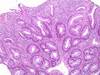

What has this kid got going on?

Peutz Jegher Syndrome

What was the cause of this polyp?

How do you know?

Peutz Jegher Syndrome

Small intestine Peutz Jegher polyps have a smooth muscle core with arborizing branches. Most polyps have a connective tissue core, so this is pretty distinct.